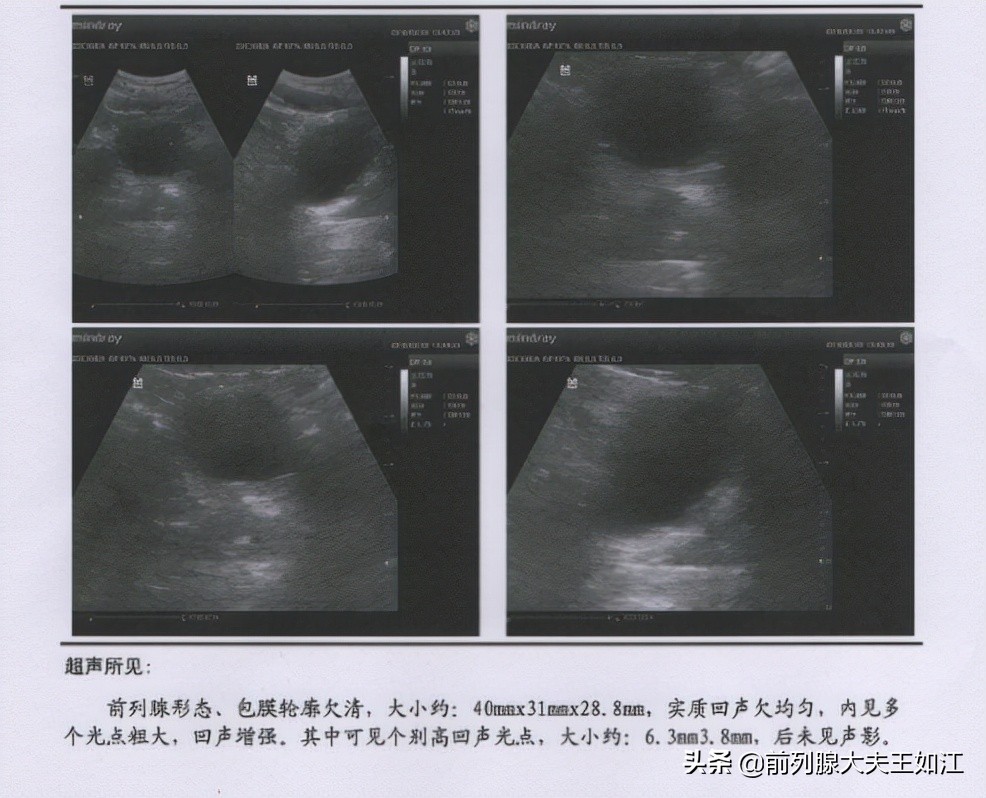

B超检查可见前列腺大小40*31*28.8mm,实质回声欠均匀,内可见多个光点粗大,回声增强,其中可见个别高回声光点,大小约6.3*3.8mm。

腺体体积比他这个年龄的正常尺寸明显偏小,腺体局部的钙化病灶也不小,腺体弹性变硬,可以确诊为前列腺萎缩伴钙化。